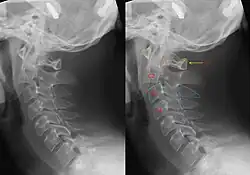

Hangman's fracture

| CT scan of hangman's fracture | |

Hangman's fracture is the colloquial name given to a fracture of both pedicles, or partes interarticulares, of the axis vertebra (C2).[1]